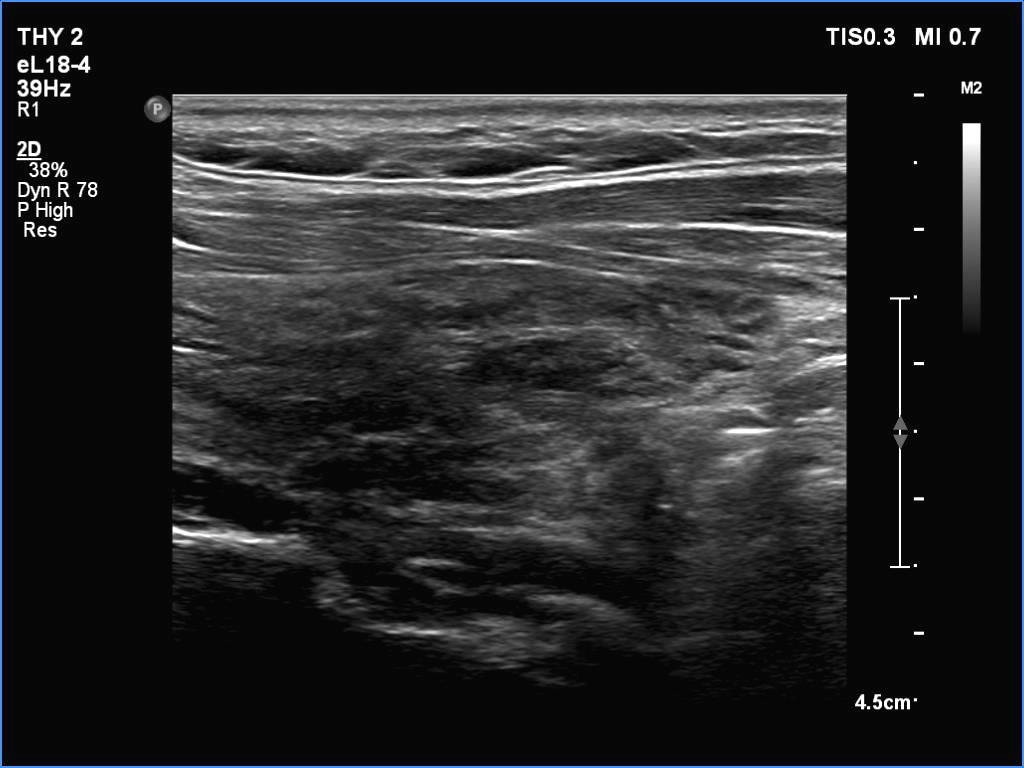

The echogenicity of the nodule - case 1177 (ultrasonographic picture 2)

Right lobe, longitudinal view.